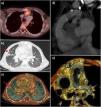

Case 1. Girl aged 4 years that had underwent the Rastelli procedure and implantation of a bovine jugular vein (BJV) graft. She developed sepsis caused by Staphylococcus aureus with evidence of a pulmonary lesion in the conventional CT scan, which was interpreted as necrotic pneumonia. The PET/CT scan detected hypermetabolic activity in the pulmonary artery graft (Fig. 1). After treatment, the patient developed symptoms again; the blood culture results were negative, but since the follow-up PET/CT scan revealed abnormalities, the final diagnosis was IE relapse, and stepwise treatment proved effective.

(a) Axial PET/CT image showing focal FDG uptake in the pulmonary graft (circle). (b) Chest CT, lung window. (c) 3D volume rendering image showing a peripheral cavitary lesion (red arrow) in the upper right lobe. (d) and (e) The retrospective interpretation of the CT scan revealed a nodular lesion suggestive of a thrombus/vegetation in the lumen of the pulmonary conduit.